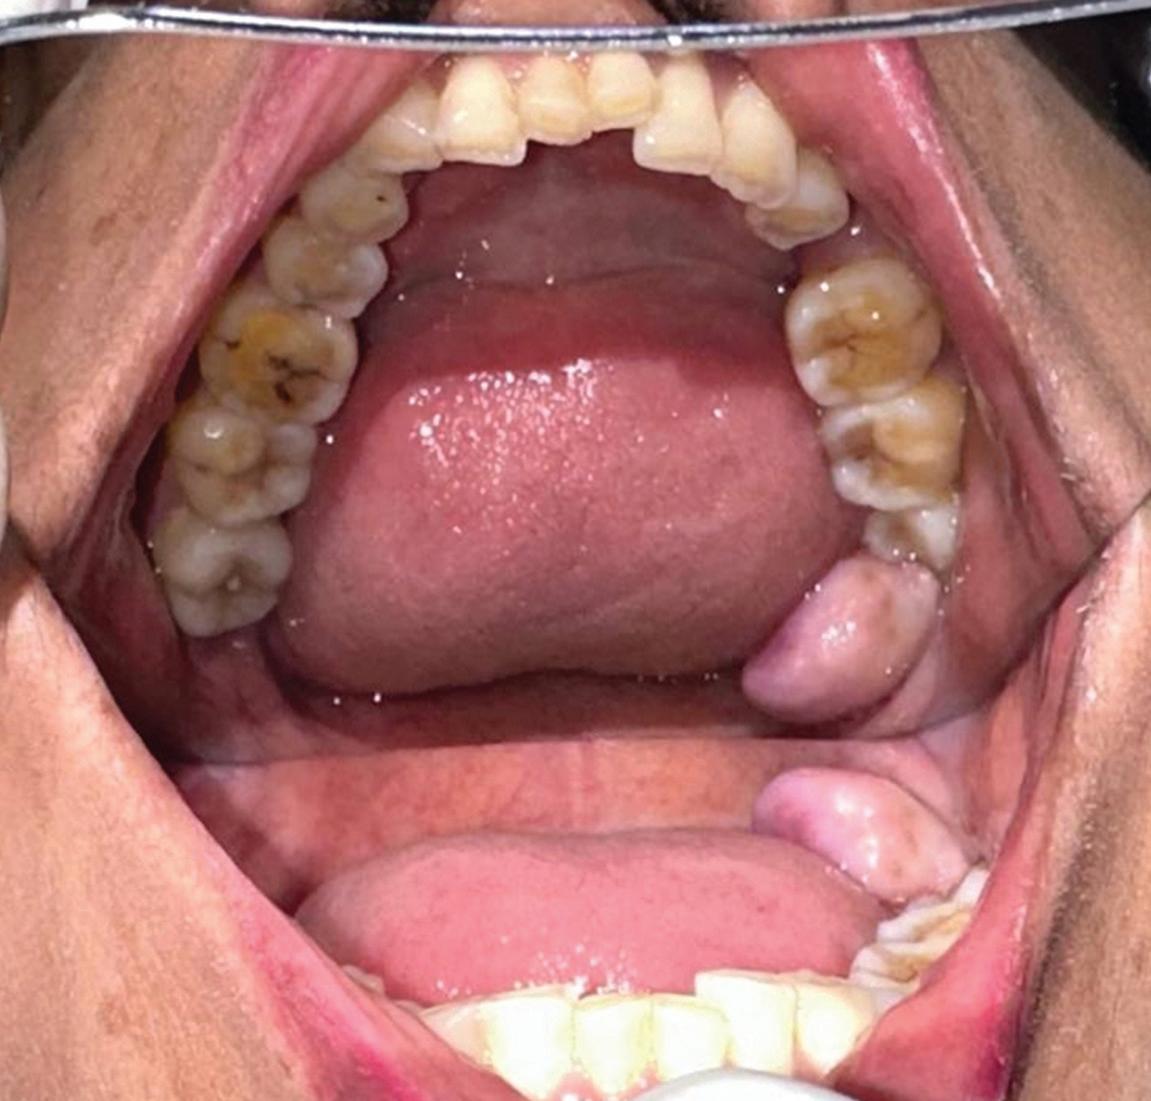

A clinical guide to oral manifestations and diagnosis of limited systemic sclerosis: a case report

Rare angiofibrolipoma of the oral cavity: a case report